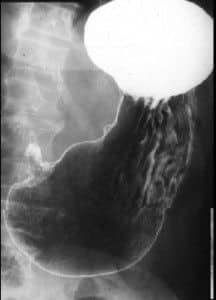

ULCUS

• ULCUS EN CURVATURA MENOR. NICHO ULCEROSO CON CONTRASTE Y PLIEGUES CONVERGENTES